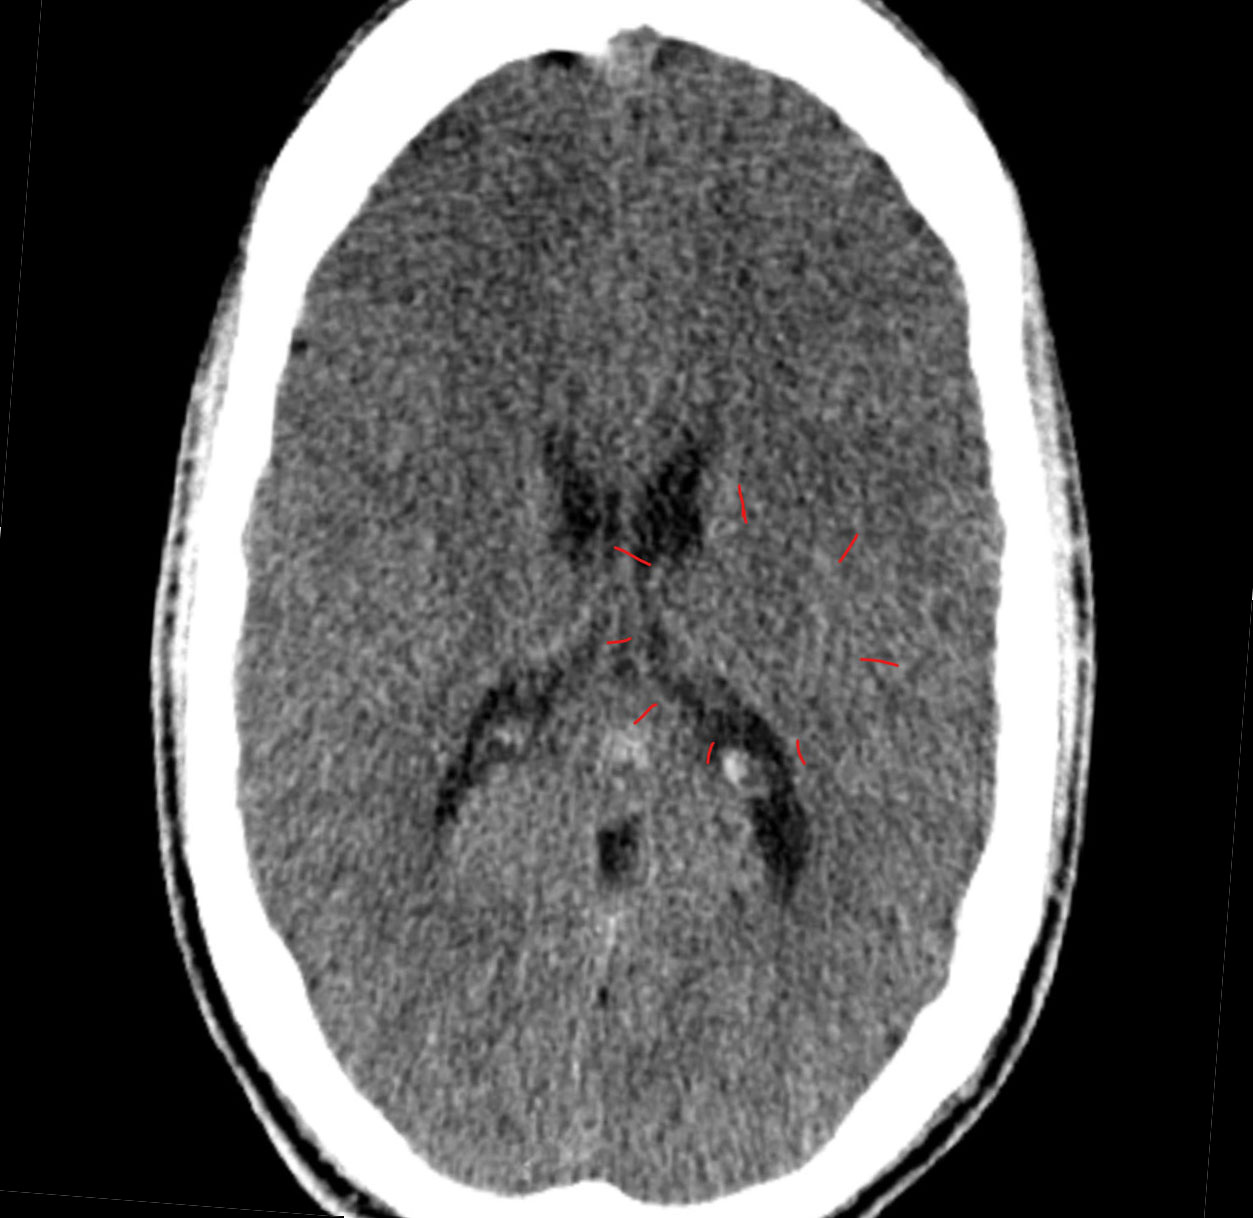

| Note | According to CM, most bone tumors are metastases (= secondary tumors). The reason for this is that people suffer local self-esteem conflicts from cancer diagnoses or by debilitating therapies (surgery, chemotherapy). E.g., after a breast cancer diagnosis: “I am no longer a real woman! “ = local self-esteem conflict with resulting cell division in the breast bone or ribs = CM‘s “bone cancer.“ Decreasing examination intervals/progressively better imaging technology ensure that these tumors are discovered sooner and more often. So-called primary bone tumors are usually discovered when a patient complains of pain. In earlier times, the patient was sent home for bed rest. Now they keep looking until they find something. In CT scans, not only are tissue-dense (hyper-dense) areas suspected of being carcinogenic but also areas with low density (hypo-dense) = CM‘s giant cell bone tumor or “osteoclastoma.“ |